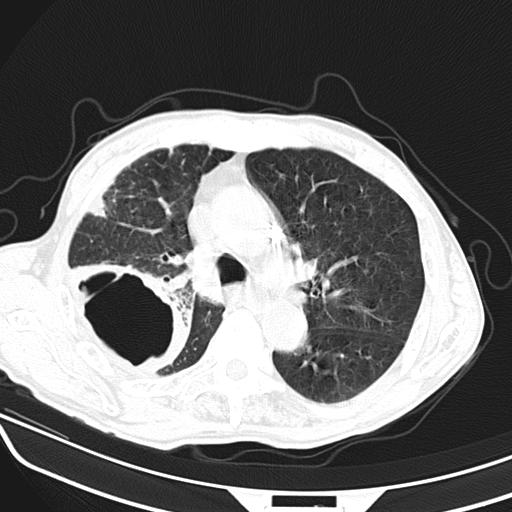

男,70,发烧咳嗽咳痰10余天,查痰结核菌阴性。否认以前有肺病史。治疗10天后症状减轻。 img]/upload/forum/2009/12/302117469692.jpg[/img]

影像所见:右上肺见一巨大厚壁空洞,内壁欠光整,右上肺广泛斑片状、大片状模糊阴影。

影像所见:右上肺见一巨大厚壁空洞,并见分隔,内壁欠光整,右上肺广泛斑片状、大片状磨玻璃阴影。

这例首先确定为感染性病变应该没问题,关键是怎么解释哪个大洞的问题。结核没有卫星病灶;脓肿没有液平;病毒感染?;真菌?;寄生虫?-----?